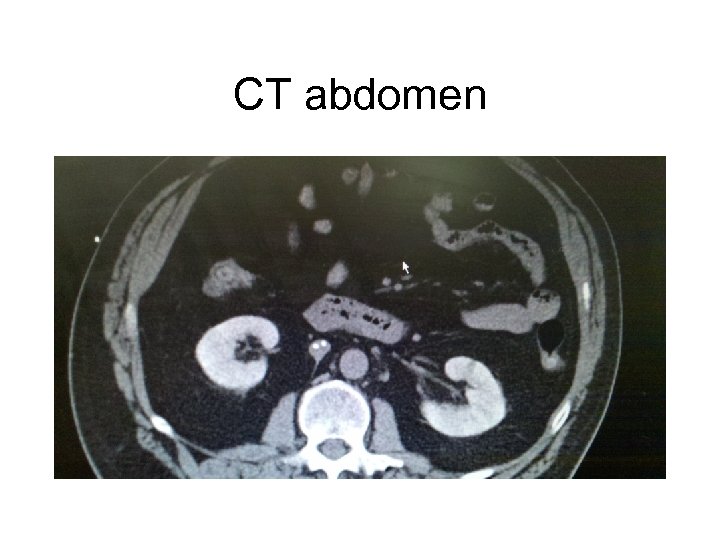

CT abdomen

How do you differentiate ARF from CRF. • What physical exam finding tells you the pt has Chronic Kidney Disease? • What Would you see on renal Imaging for a pt with CKD?